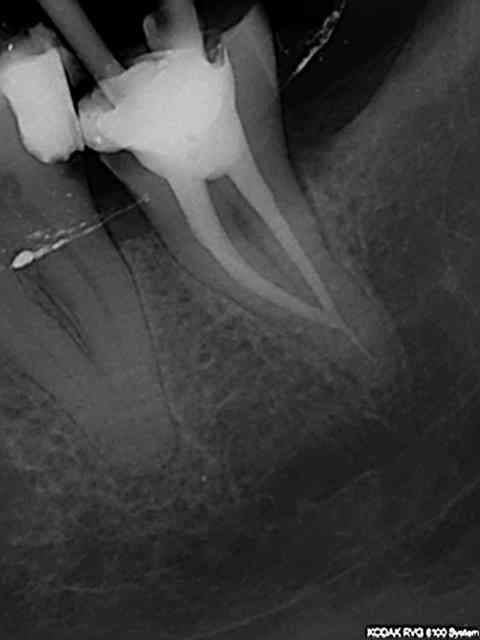

Et une de plus !